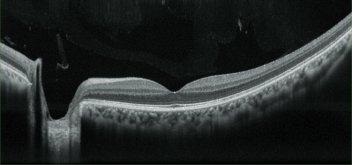

High definition images

For OCT imaging, up to 50 images can be averaged and the OCT sensitivity is selectable among ultra fine, fine, and regular sensitivities based on ocular pathology. The Retina Scan Duo™ has a built-in 12-megapixel CCD camera, producing high quality fundus images.